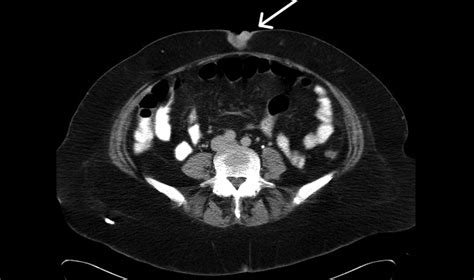

The human body often communicates the presence of underlying systemic disease through subtle, external indicators that can easily be overlooked. Among these clinical signs, the Sister Mary Joseph Nodule stands out as a rare but highly significant physical manifestation. Named after a surgical assistant to Dr. William Mayo, this clinical sign typically presents as a palpable, firm nodule located at the umbilicus. It serves as a stark warning sign, often indicating an advanced, metastatic malignancy originating from within the abdominal or pelvic cavities. Recognizing this nodule early is crucial, as it often alters the trajectory of patient care and diagnostic urgency.

The Sister Mary Joseph Nodule is not a primary skin condition but rather a secondary metastasis. Patients typically present with a painless or occasionally tender umbilical mass that has developed over weeks or months. Because the umbilicus is a relatively non-distinctive area of the body, patients may initially mistake these lumps for common benign conditions such as hernias or granulomas. However, clinical characteristics that raise suspicion include:

• Imaging Studies: A Contrast-enhanced CT scan of the abdomen and pelvis is the gold standard for identifying the primary tumor site and assessing the extent of metastatic disease.

• Biopsy: Fine-needle aspiration (FNA) or an excisional biopsy of the umbilical nodule is essential for histological confirmation and immunohistochemical analysis.